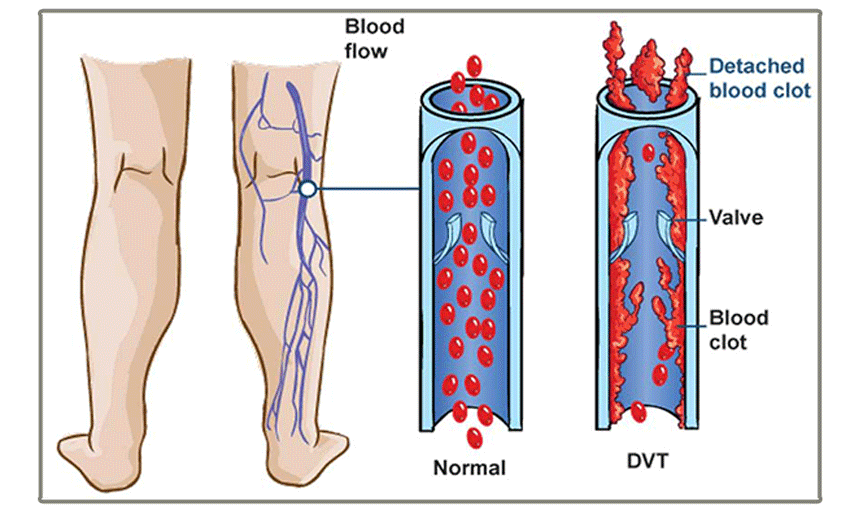

thrombosis vein causes netmeds syndrome

vein thrombosis deep dvt danger clot blood prevention

dvt thrombosis vein

thrombosis vein dvt blood